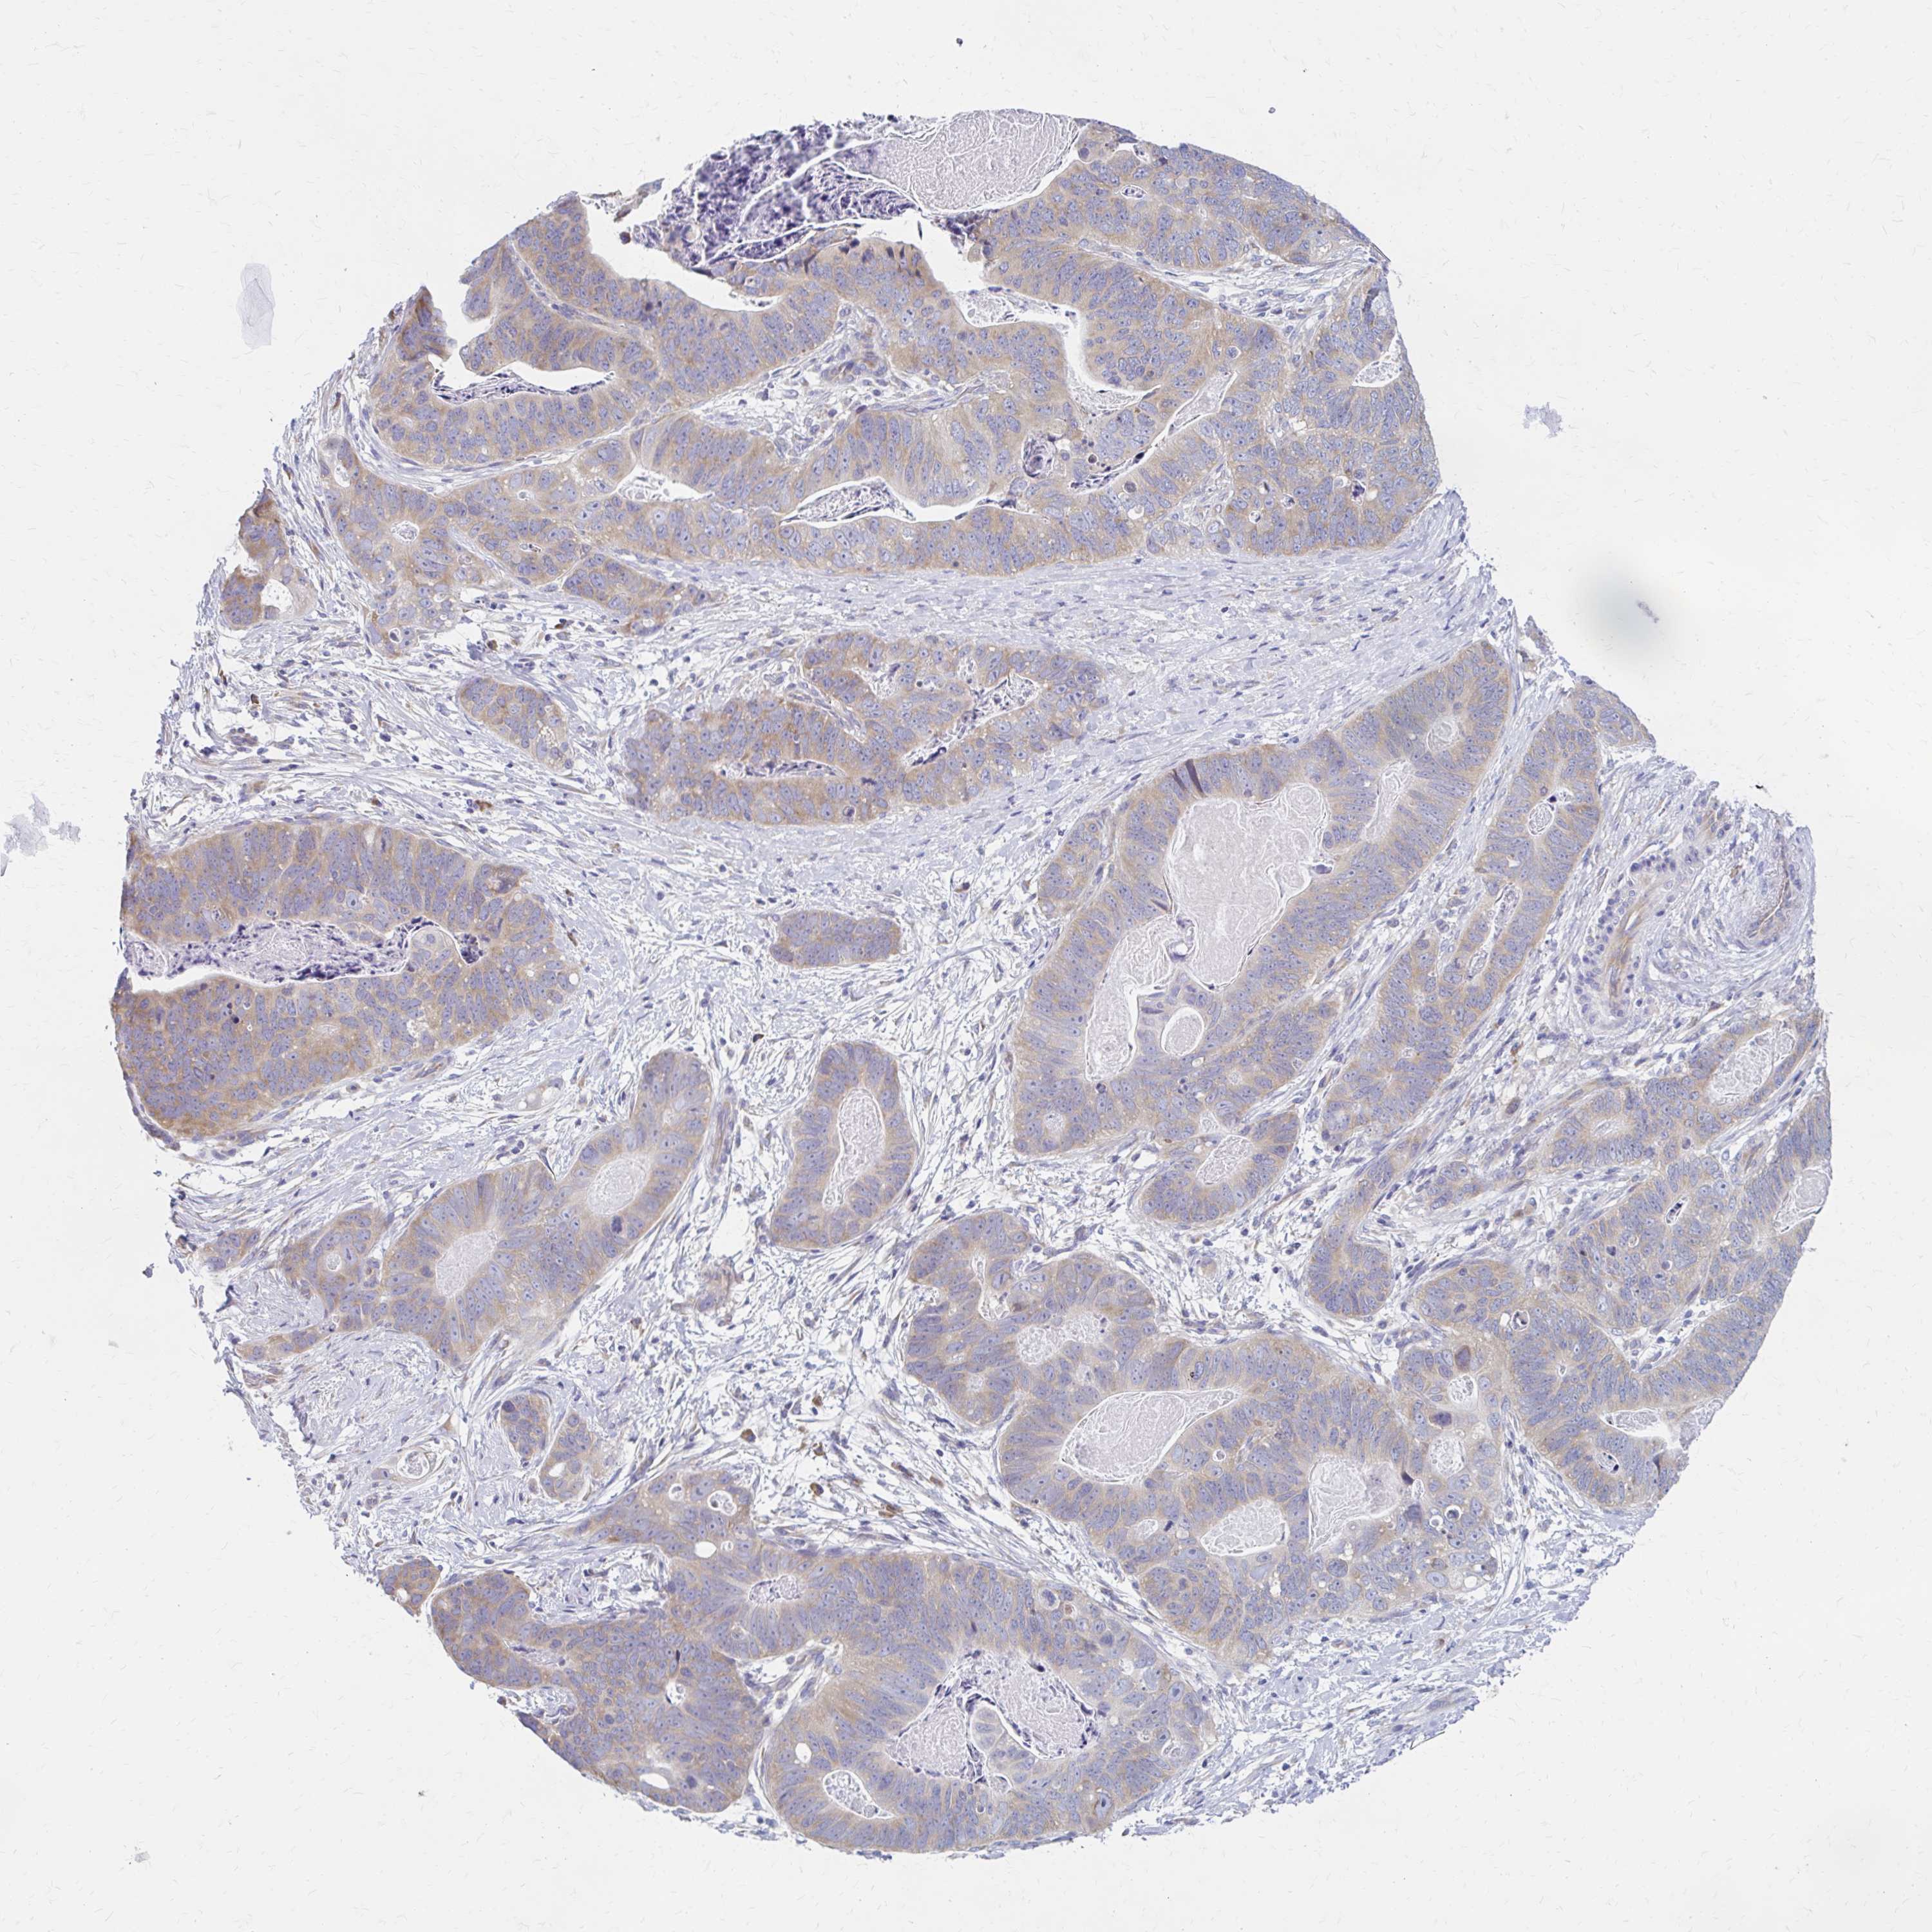

STOMACH CANCER - Protein expressioni

A mouse-over function shows sample information and annotation data. Click on an image to view it in a full screen mode. Samples can be filtered based on level of antibody staining by selecting one or several of the following categories: high, medium, low and not detected. The assay and annotation is described here.

Note that samples used for immunohistochemistry by the Human Protein Atlas do not correspond to samples in the TCGA dataset.

Antibody stainingi

Antibody staining in the annotated cell types in the current human tissue is reported as not detected, low, medium, or high, based on conventional immunohistochemistry profiling in selected tissues. This score is based on the combination of the staining intensity and fraction of stained cells.

Each image is clickable and will lead to virtual microscopy that enables deeper exploration of all samples and also displays staining intensity scores, fraction scores and subcellular localization as well as patient and tissue information for each sample.

Antibody HPA060776

Antibody HPA063379

Staining

High

Medium

Low

Not detected

Intensity

Strong

Moderate

Weak

Negative

Quantity

>75%

75%-25%

<25%

None

Location

Nuclear

Cytoplasmic/membranous

Cytoplasmic/membranous,nuclear

Adenocarcinoma, NOS